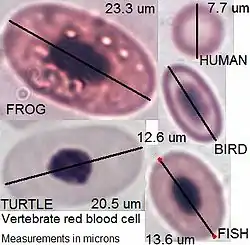

In non-mammals

Human blood is typical of that of mammals, although the precise details concerning cell numbers, size, protein structure, and so on, vary somewhat between species. In non-mammalian vertebrates, however, there are some key differences:[19]

- Red blood cells of non-mammalian vertebrates are flattened and ovoid in form, and retain their cell nuclei.

- There is considerable variation in the types and proportions of white blood cells; for example, acidophils are generally more common than in humans.

- Platelets are unique to mammals; in other vertebrates, small nucleated, spindle cells called thrombocytes are responsible for blood clotting instead.